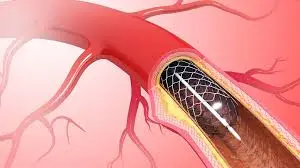

Genicular Artery Embolization is a minimally invasive procedure used to relieve pain in the knee, which is, in most instances, related to knee osteoarthritis, by extinguishing the abnormal blood vessels adding to the inflammatory processes of the lining of the knee joint, known as the synovium.

Advanced osteoarthritis can lead to increasing amounts of inflammation within the knee, and, as a consequence, the abnormal growth of accessory blood vessels in the regions of the inflammation can develop. These blood vessels may be associated with pain pathways and ongoing inflammatory signals. GAE works by selectively reducing blood flow in those abnormal, inflamed micro-vessels while preserving the overall blood supply needed for healthy tissues. It acts to reduce pain caused by inflammation and thereby improves function.

It is not “joint replacement,” it does not change your bone structure directly, and it does not mechanically rebuild cartilage. Rather, it targets one important driver of pain-inflammation supported by abnormal vascularity. Because GAE is performed through a small puncture and guided with imaging, many patients opt for it as a non-surgical option when they need pain relief but prefer to avoid or delay knee replacement surgery.

The question many patients ask is, “How can reducing blood flow reduce knee pain?” The answer has to do with the relationship between inflammation and abnormal vascular growth. In most cases of osteoarthritis, the lining of the knee joint becomes inflamed and develops increased micro vascularity. Those abnormal vessels can maintain inflammation and are often associated with pain signaling.

The interventional radiologist accesses an artery through a tiny puncture, often at the groin area or wrist, depending on technique and suitability. Guided by real-time imaging, a thin catheter is advanced to the arteries supplying the knee region, called the genicular arteries. The doctor then identifies small branches that show abnormal vascularity linked to inflamed synovium.

With the confirmation of the target vessels, very small embolic particles are delivered that selectively reduce blood flow in those abnormal vessels. This controlled reduction aims to decrease inflammation-driven pain over time. Because the treatment is precise and image-guided, it is designed to minimize impact on normal blood supply.